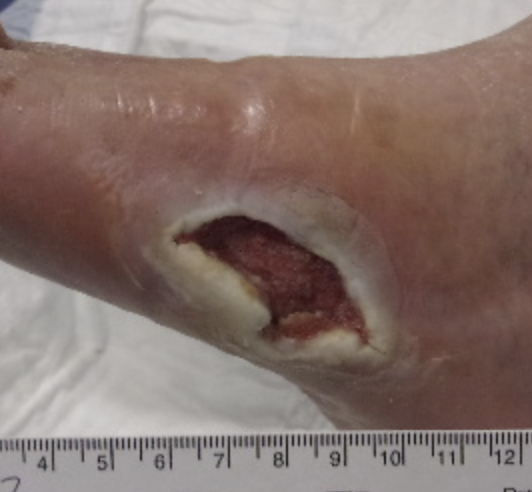

Case 3. Patient 3 is a 69-year-old male who presented with a chronic, infected fifth metatarsal wound. Surgical and clinical debridements resulted in minimal wound changes, and NPWT at -125mmHg was initiated. The wound area at this time was 15cm2 (see seventh photo above). After two weeks of NPWT, we increased the pressure to -175mmHg. This resulted in a significant reduction in wound area to 11.4cm2 after one week of increased pressure (24 percent area decrease, see eighth photo). NPWT continued until the wound bed was level with the periwound skin level. This patient continues to heal without complication.